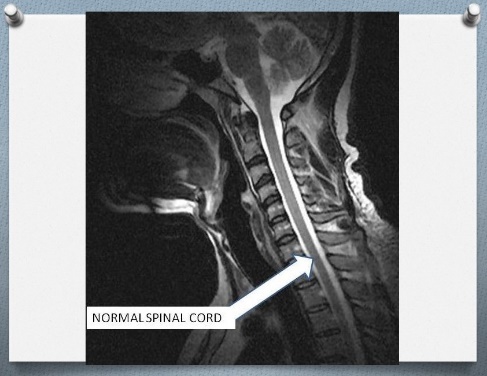

NORMAL MRI SCAN OF THE NECK

The spinal cord travels from the brain through the bones in the neck. This is like the road from Abuja airport to the stadium where it then branches in so many directions. You know how beautiful the road is to drive on and you can now get to Garki in about 30 minutes.

Anyway, the spinal cord travels through the bones in the neck. The bones are placed one on top of the other just like the way we build houses and joined with cement. Now, imagine if the cement has worn out, you find the wall is not stable anymore. The blocks can also start shifting forwards or backwards. Wobbly!